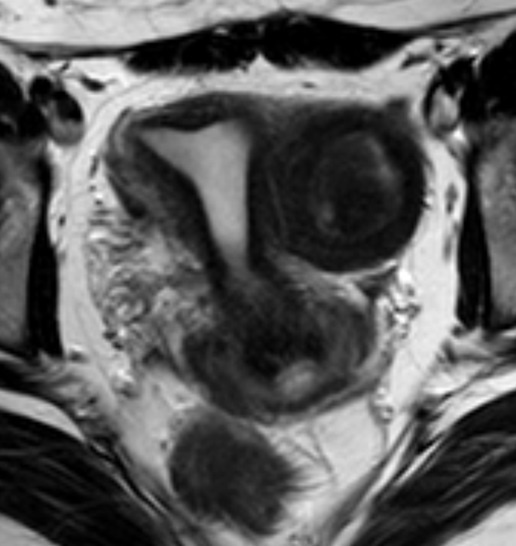

Пациентка 26 лет с клиникой остро возникших тазовых болей. Результаты УЗИ органов малого таза - тубоовариальный абсцесс, гидросальпинкс, внематочная беременность, эндометриоидная киста. По результатам УЗИ-данных и клинической картины пациентке выполнена диагностическая лапаротомия на основание которой выставлен диагноз - интрамуральная миома матки. После лапаротомия пациентка направлена на МРТ органов малого таза. На МР-изображениях в левом ребре матки определяется интрамуральное объемное образование округлой формы с жидкостным содержимым гипо- и гиперинтенсивного МР-сигнала на T2 и T2 SPIR ВИ (рис. А и Б соответственно) и однородно гиперинтенсивного сигнала на T1 и T1 с подавлением сигнала от жировой ткани ВИ (рис. В и Г соответственно). МР-картина соответствует миоме матки с внутриузловым кровоизлиянием.

На МР-изображениях в левом ребре матки определяется интрамуральное объемное образование округлой формы с жидкостным содержимым гипо- и гиперинтенсивного МР-сигнала на T2 и T2 SPIR ВИ (рис. А и Б соответственно) и однородно гиперинтенсивного сигнала на T1 и T1 с подавлением сигнала от жировой ткани ВИ (рис. В и Г соответственно). МР-картина соответствует миоме матки с внутриузловым кровоизлиянием.